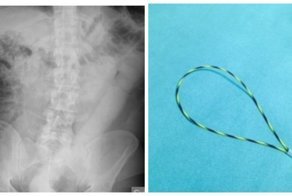

- Врачам пришлось изобрести новый инструмент, чтобы извлечь из мужчины дилдо